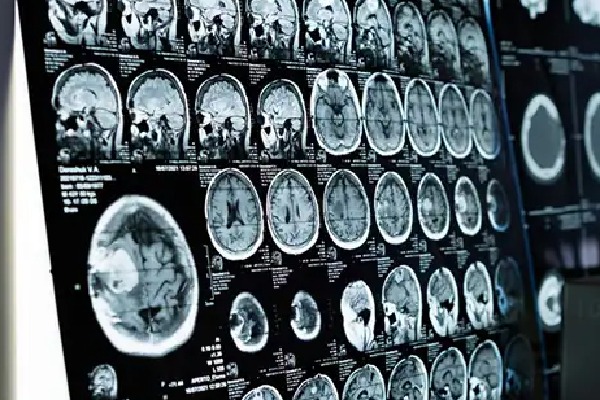

స్వేచ్ఛగా జీవించే ఏక కణ జీవి అమీబా కారణంగా కేరళలోని అలప్పుజాలో అరుదైన బ్రెయిన్ ఇన్ఫెక్షన్ సోకి ఓ యువకుడు మృతి చెందినట్లు ఆ రాష్ట్ర ఆరోగ్య మంత్రి వీణా జార్జ్ తెలిపారు. అలప్పుజాలోని పానవల్లి తీర ప్రాంతానికి చెందిన పదిహేనేళ్ల బాలుడు ప్రైమరీ అమీబిక్ మెనింగోఎన్సెఫాలిటిస్ అనే వ్యాధి బారినపడ్డాడు. బాలుడి మరణాన్ని మంత్రి ధృవీకరించారు. అలాగే రాష్ట్రంలో ఇంతకుముందు ఐదు అరుదైన ఇన్ఫెక్షన్ కేసులు నమోదైనట్లు తెలిపారు.

ఇన్ఫెక్షన్కు కారణమయ్యే అమీబా ఏక కణ జీవులు నిశ్చల నీటిలో కనిపిస్తాయని మంత్రి తెలిపారు. డాక్టర్లు చెప్పిన వివరాల ప్రకారం... స్వేచ్ఛా జీవి, నాన్-పారాసిటిక్ అమీబా బ్యాక్టీరియా ముక్కు ద్వారా శరీరంలోకి ప్రవేశించి, మనిషి మెదడుకు ఇన్ఫెక్షన్ కలుగజేస్తుంది.